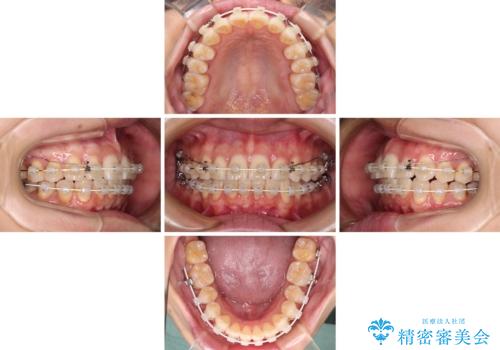

- 矯正装置

- 審美装置

- 治療計画

- 奥歯の咬み合わせと、上下前歯の隙間を気にして来院された患者様です。

上顎の歯列全体が、下顎歯列に対して前方に位置しており、その影響で上顎前歯がやや前方に突出している状態でした。

横顔の印象から、抜歯をして積極的に口元を引っ込める必要はなかったため、アンカースクリューを用いて上顎歯列全体を後方に移動させることとしました。